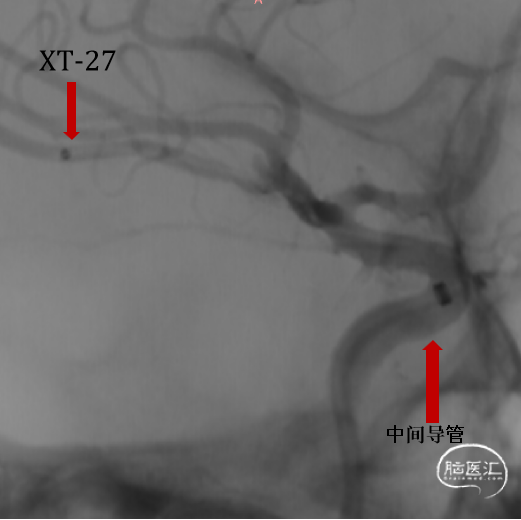

支架微导管:XT-27 with Synchro2 Standard

通路建立:

将长鞘Target置于颈内动脉C3段。

泥鳅导丝+5F 125cm造影管+6F中间导管到达颈内动脉海绵窦前曲段,撤出泥鳅导丝及125cm造影导管。

Synchro2+XT-27通过中间导管超选至动脉瘤远端,撤出导丝。